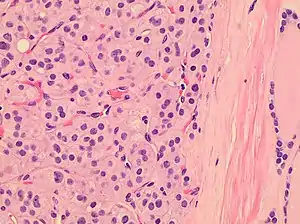

| Histopathology of a Hürthle cell adenoma | |

Hürthle cells are characterized as enlarged epithelial cells. These cells, when stained with hematoxylin-eosin show as pink. This is due to the abundant mitochondria and granular eosinophilic matter within the cells' cytoplasm. These cells are often found in the thyroid. The thyroid is a butterfly-shaped organ, responsible for producing various hormones for metabolism. These cells are often benign, but they can be malignant and metastasize. Hürthle cells are resistant to radiation, but can be treated using radioactive iodine treatment.[4]